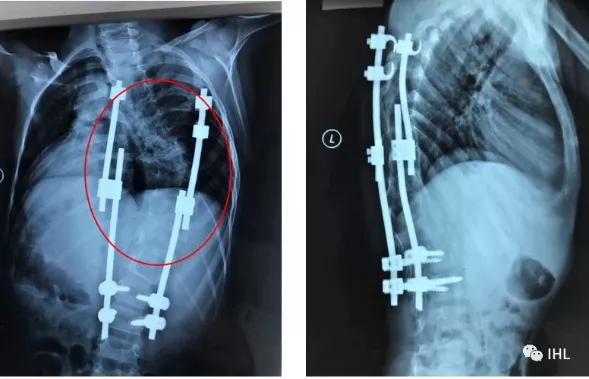

以下是一个 1型神经肌纤维瘤病(NF1)引起的早发型脊柱侧凸(EOS)的14岁孩子的X片,在过去的6-7年里,他至少在国内不同医院接受了3次以上的手术治疗,但由于内固定的植入的效果不理想,几年间,他的脊柱不仅畸形没有得到很好的改善,反而在腰段出现了明显的前凸倾向。

2009年接受了第一次脊柱手术之后的X光影像,这时他脊柱胸段的侧突曲线(红框处)还非常明显。

2013年在当地医院最后一次翻修手术后的的X光片,脊柱的侧凸稍有改善,但在腰椎段(红框处)开始出现前凸和矢状面失衡的倾向。